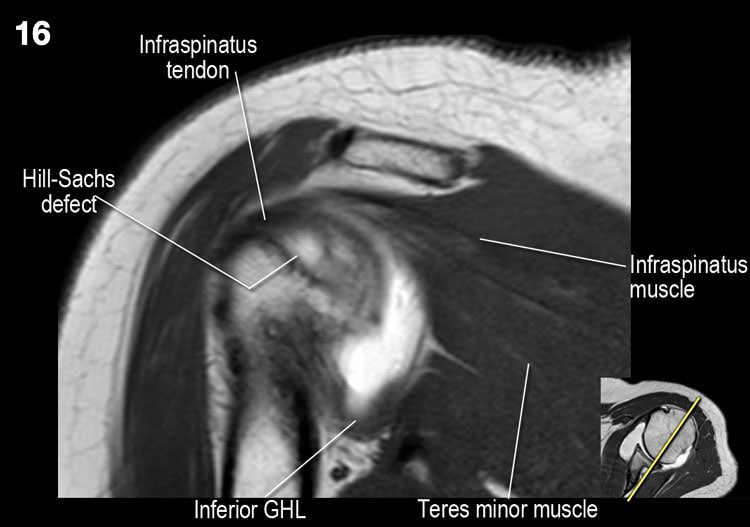

Hình ảnh mặt sau

Hình ảnh thể hiện các cơ và gân của cơ trên gai, cơ dưới gai và cơ tròn bé. Tất cả đều bám vào mấu động lớn.

Ở mức này, cũng tìm kiếm tổn thương Hill-Sachs ở bờ sau-ngoài của chỏm xương cánh tay. - Các thớ sợi của gân cơ dưới vai giữ gân cơ nhị đầu trong rãnh của nó. Đánh giá sụn khớp.

Tổn thương Hill-Sachs chỉ được thấy ở mức mỏm quạ.

- Lưu ý tổn thương Hill-Sachs nhỏ.